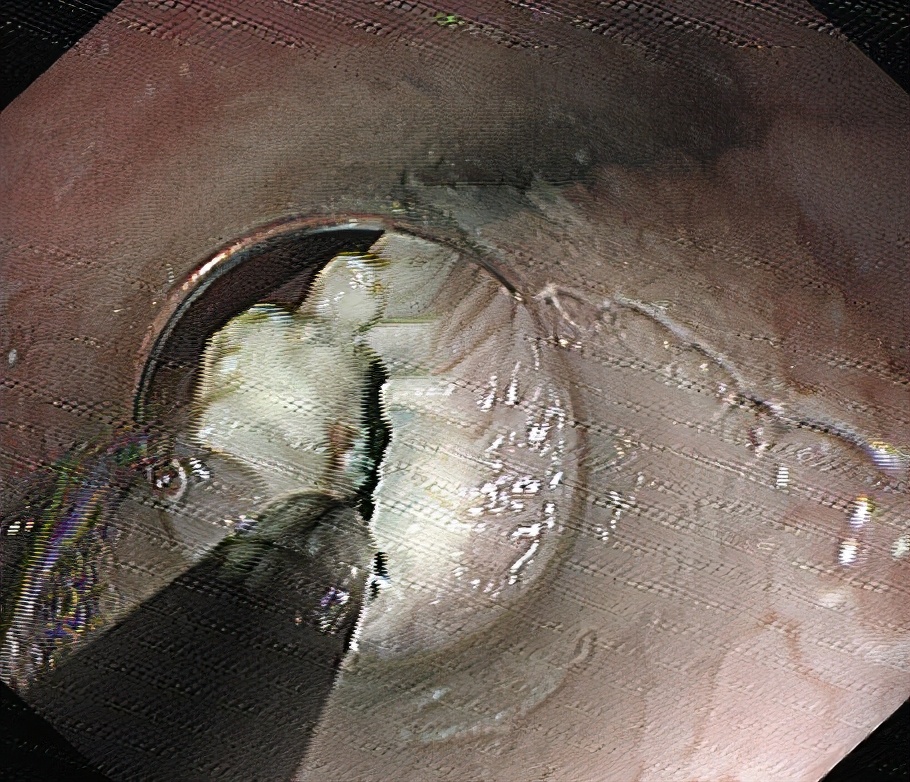

03

分离粘膜下层,建立黏膜下“隧道”。